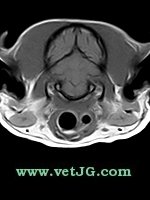

RESONANCIA MAGNÉTICA

AXIAL